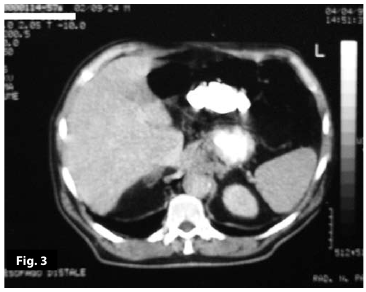

Figure3

Figure4

Figure3-4